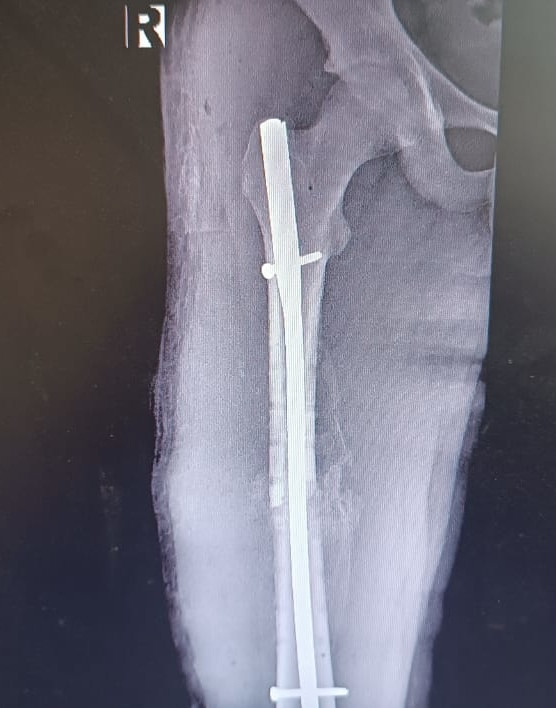

Уже 18 сентября 2025 года врачи – Косимов Ойбек Толибович и Смирнов Максим Андреевич – успешно провели такую операцию ребёнку с переломом бедра, полученным в результате ДТП (столкновение мотоцикла с легковым автомобилем).